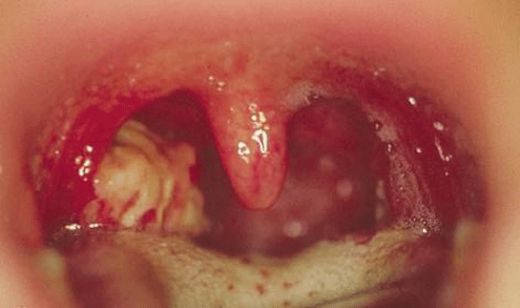

Tedavi Yöntemleri Bademcik iltihabının tedavisi, iltihabın nedenine bağlı olarak değişiklik göstermektedir. Genel olarak kullanılan tedavi yöntemleri şunlardır:

Ek Bilgiler Bademcik iltihabı, bazen diğer sağlık sorunlarına yol açabilir. Örneğin, bademciklerin sürekli iltihaplanması, uyku apnesi gibi sorunlara neden olabilir. Bu nedenle, bademcik iltihabı belirtileri görüldüğünde bir sağlık profesyoneline başvurulması önemlidir. Ayrıca, bademcik iltihabının tedavisi sırasında evde uygulanabilecek doğal yöntemler de mevcuttur, ancak bu yöntemlerin etkili olup olmadığını değerlendirmek için mutlaka bir doktora danışılması önerilmektedir. Bademcik iltihabı, genellikle geçici bir durum olmasına rağmen, tekrarlayan vakalar veya ciddi semptomlar durumunda profesyonel tıbbi yardım alınması gerekmektedir. Tedavi yöntemleri, hastanın genel sağlık durumu, yaş ve belirtilerin şiddetine göre belirlenmektedir. |